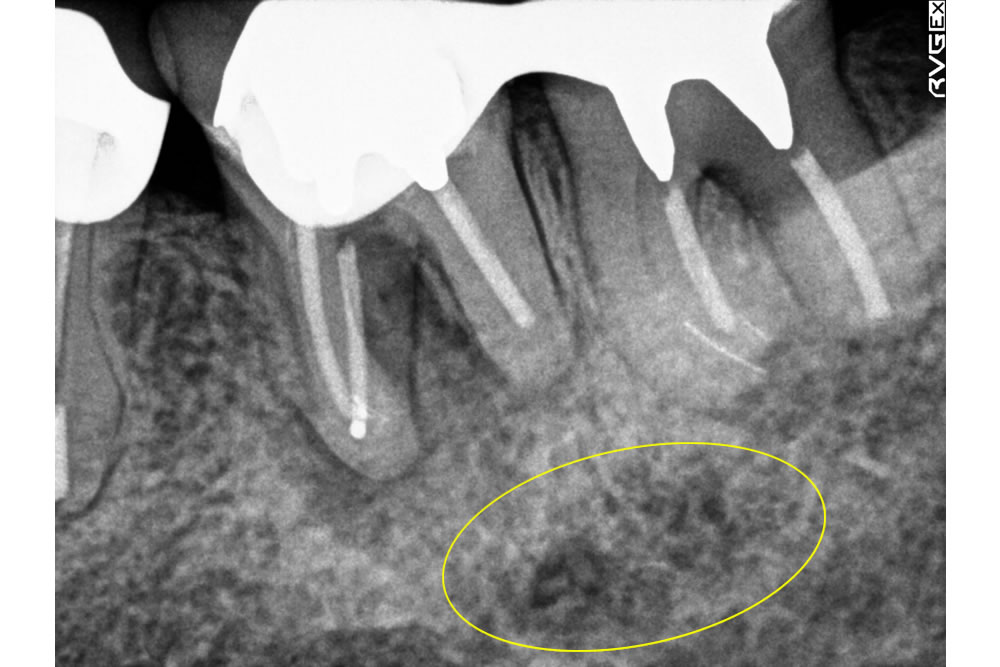

また、根管治療を終えた際にも再度レントゲン写真を撮り状態を確認します。歯の根の先の黒い影が以前より縮小してきていることが確認できます。